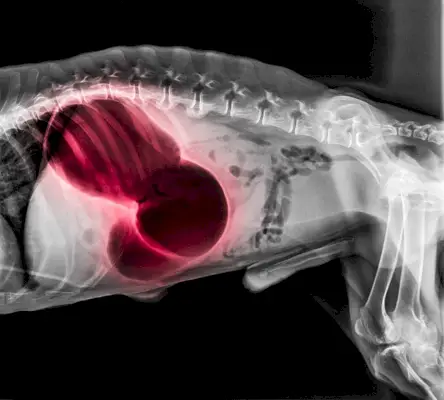

Standard røntgenbilder er stillbilder som brukes som en del av den diagnostiske prosessen for å finne ut om et bein er brukket eller identifisere betydelige endringer i hundens organer.

Bildekreditt: Intarapong, Shutterstock